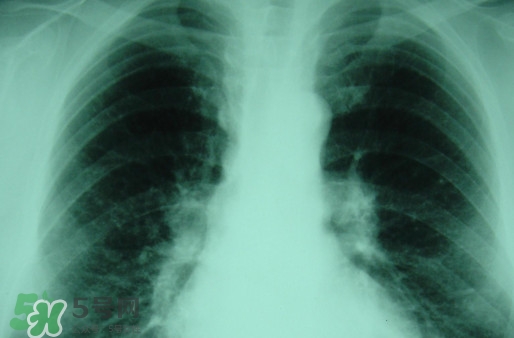

塵肺病多半是肺部灰塵太多導致肺部承載大清理工作降低導致的,對此有人提出換肺治療的方法。那么,塵肺病能換肺治愈嗎?塵肺病不能吃什么?

塵肺病能換肺治愈嗎

塵肺病換肺理論上可行,實際中也可以操作,但那是有錢人的游戲

目前換肺治療塵肺病是有的,但壽命啥的都會有影響

而且你要找到適合的供體也很難。